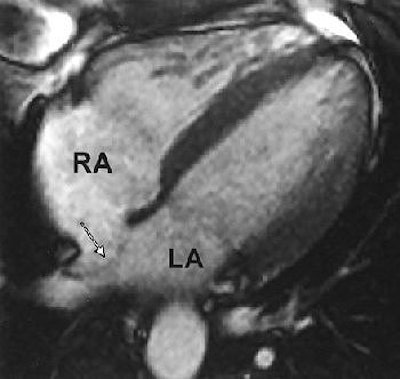

| Thirty-two-year-old man with atrial septal aneurysm (arrow) on MRI. Typical bulging of atrial septum is shown toward left atrium in horizontal long axis (LA; RA = right atrium). Mohrs OK, Petersen SE, Erkapic D, Rubel C, Schräder R, Nowak B, Fach WA, Kauczor HU, Voigtlaender T, "Diagnosis of Patent Foramen Ovale Using Contrast-Enhanced Dynamic MRI: A Pilot Study" (AJR 2005; 184:234-240). |

The results showed that PFO was visually identified in all 15 patients, and excluded in the control group on MRI. For the patients with PFO, "an early contrast enhancement due to intracardiac right-to-left shunting was present in the left atrium before the contrast agent reached the pulmonary veins," the authors wrote. There was a 20% prevalence of atrial septal aneurysm in the PFO population, and MRI correctly identified these cases.